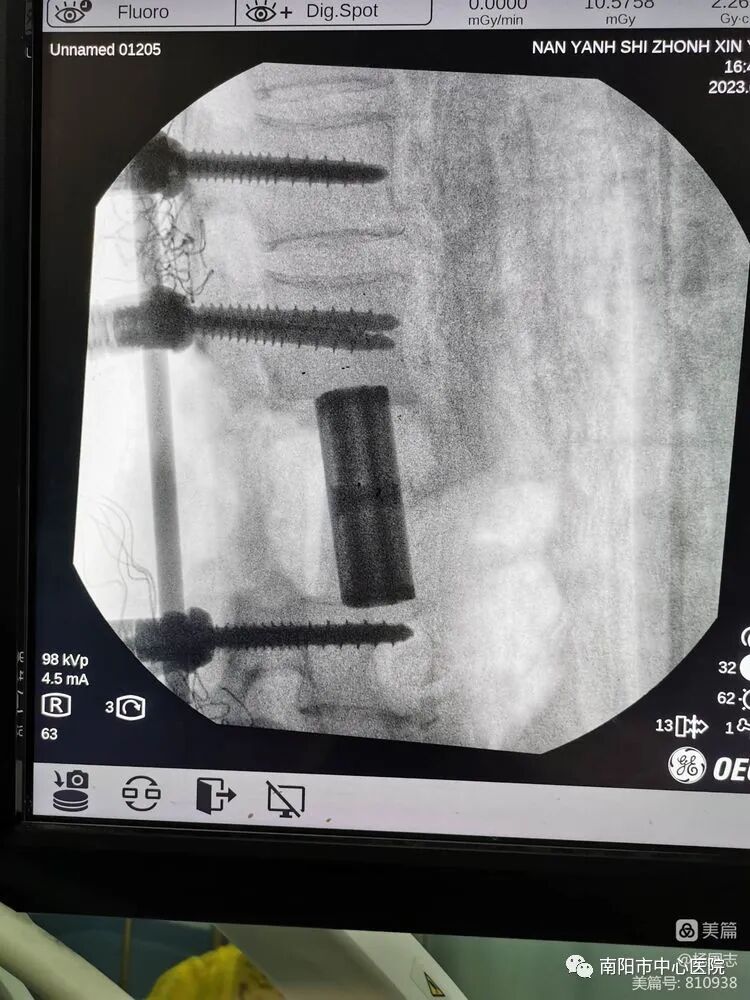

脊柱惡性腫瘤手術(shù)是當(dāng)今脊柱外科最有風(fēng)險(xiǎn)和挑戰(zhàn)的手術(shù)之一,由于其特殊的解剖部位,被認(rèn)為是完整切除的“手術(shù)禁區(qū)”。近日,南陽市中心醫(yī)院骨二科團(tuán)隊(duì)在尹銳峰主任的領(lǐng)導(dǎo)和支持下,在麻醉科,放射科,腫瘤內(nèi)科等專業(yè)協(xié)同診治下(MDT),成功為一名脊柱腫瘤患者實(shí)施全單一后路脊柱腫瘤整塊切除術(shù)(TES)。TES 是指椎體腫瘤大塊完整切除術(shù),是經(jīng)兩側(cè)椎弓根切除后,以整塊的形式將存在于一個(gè)脊椎間室內(nèi)的腫瘤及其周圍病灶完整切除,在腫瘤學(xué)上是邊緣切除或廣泛切除的概念,對(duì)于降低局部復(fù)發(fā)率有重要意義,而對(duì)手術(shù)醫(yī)生的手術(shù)技術(shù)有很高的要求,加之脊柱腫瘤的 En - bloc切除顯露困難,脊髓及大血管損傷風(fēng)險(xiǎn)極大,國內(nèi)開展此項(xiàng)技術(shù)的醫(yī)院不多。其適應(yīng)癥,WBB分期9-4區(qū)或者10-5區(qū),Tomita分型2-5型的病例是一種理想的方式。

腰3椎體骨質(zhì)破壞,轉(zhuǎn)移癌,單發(fā)椎體骨質(zhì)破壞,寡病灶